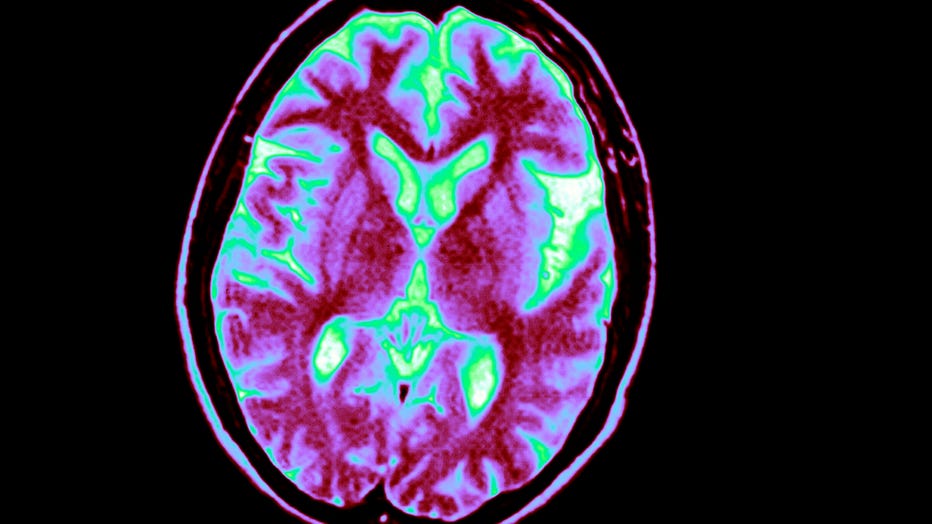

Alzheimers disease, as shown on an MRI. (Photo By BSIP/UIG Via Getty Images)